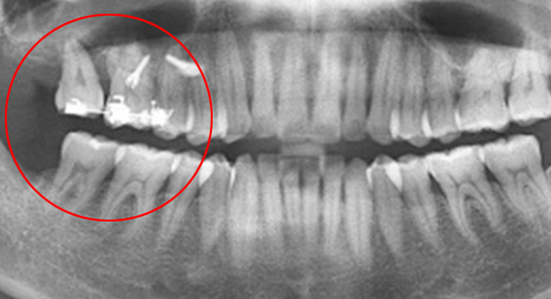

치조골 손상이 심해 발치를 하고 임플란트를 해야 하는 상황

인접치아로 발치된 공간을 메움

46세 남성환자로 상악동 거상술과 임플란트 진단을 받은 상태로 내원. 치조골이 2/3이상 오염되어 살릴 수 없어 발치를 진행, 인접치아를 움직여 발치 된 공간을 닫는 교정치료를 시행하였습니다.